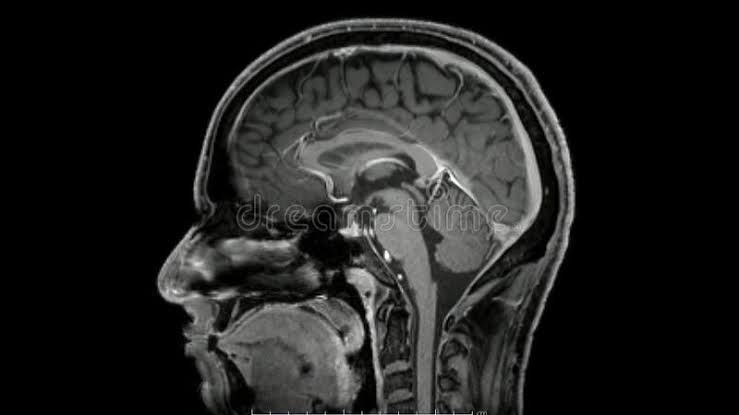

Neurocirugía

Tumores cerebrales

Enfermedades Cerebrovasculares

Aneurismas Cerebrales

Hidrocefalia

Neuralgia del Trigémino